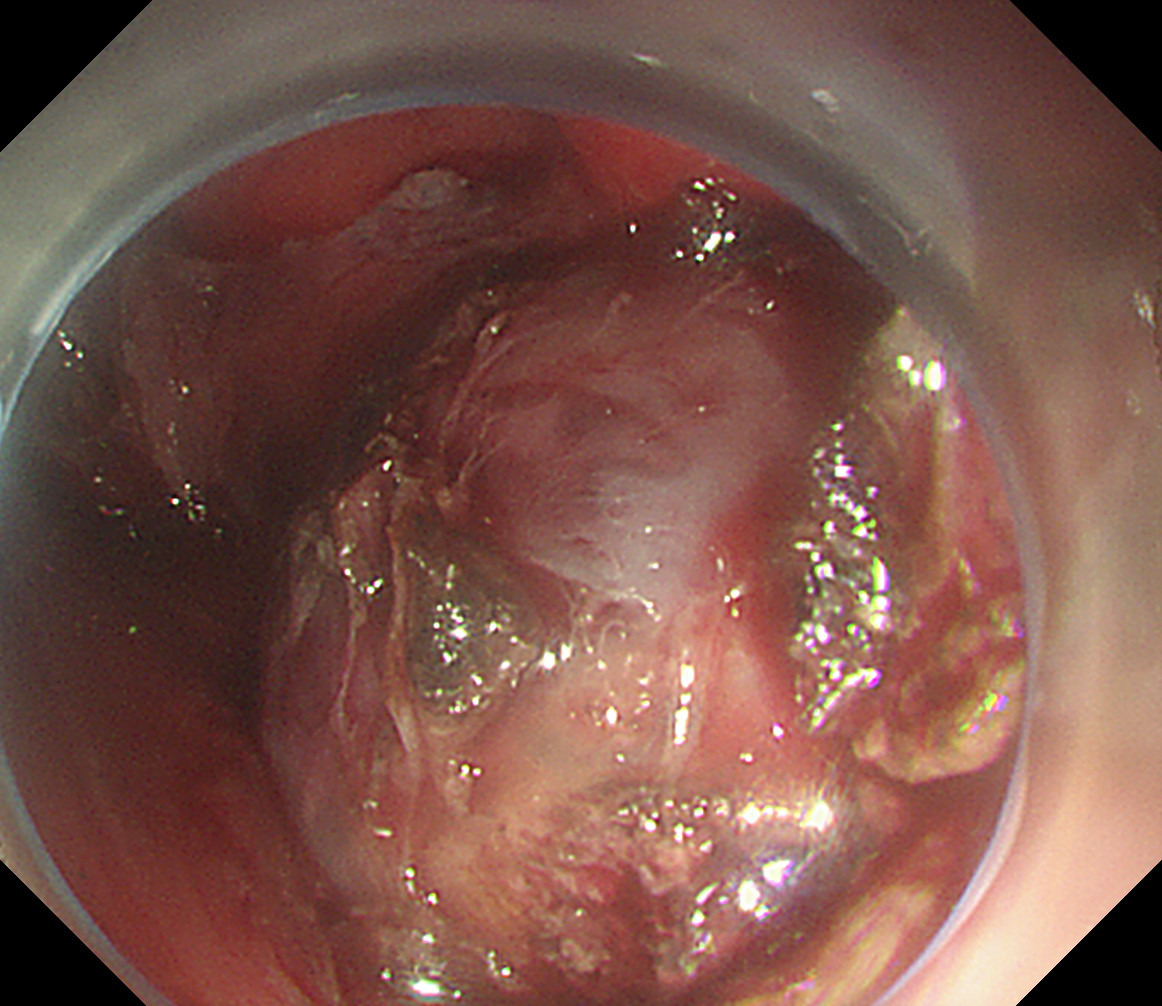

术中剥离瘤体

经过充分的准备,在麻醉科、普外科的支持下,刘鹏主任带领消化科内镜医护团队为龙女士实施了手术。术中用胃镜经口进入胃内找到病变压迫位置,在胃壁上切一个切口以便于胃镜顺利进入腹腔,观察到肿瘤组织基本全部位于胃外,然后逐层分离肿瘤组织,仅一小时不到将肿瘤完整地剥离。由于瘤体过大,切除后难以拖入胃腔,通过贲门困难。刘鹏主任巧妙地使用圈套器通过胃镜钳道口穿过胃壁切口将瘤体完整拖入胃腔,再用取石网篮将瘤体通过胃和食管,从患者的嘴巴里掏了出来后,再用数枚钛夹完美地闭合了的创面。精湛、细致的手术技巧,娴熟的瘤体切除步骤,果断的血管预先电凝处理,让整个术中未见明显出血,同时保留了器官功能。